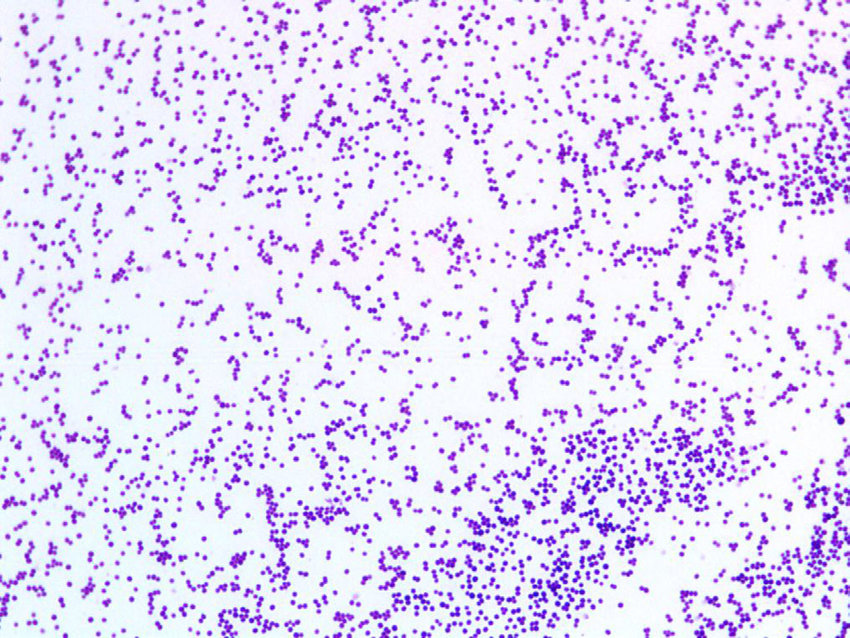

Streptococcus pneumoniae

Staphylococcus aureus